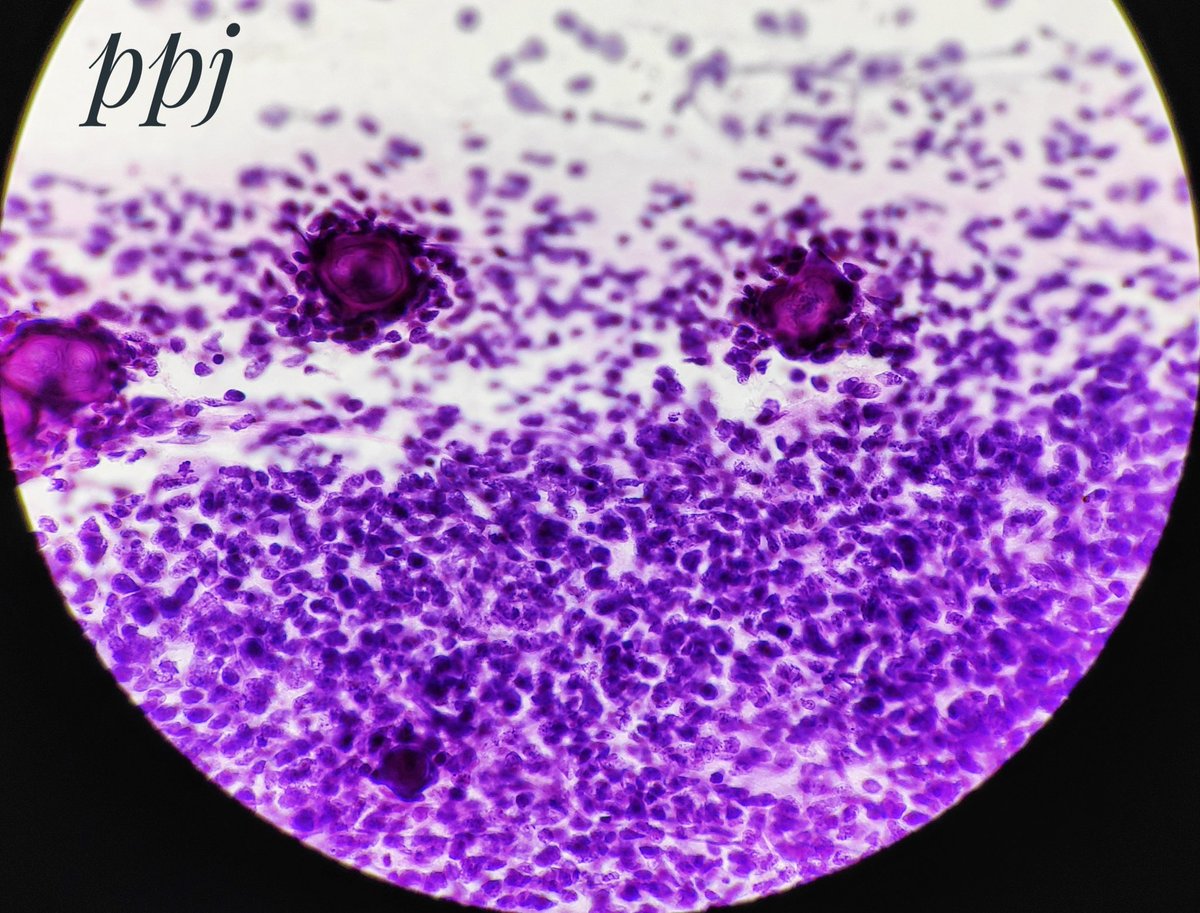

Cerebellar mass in an older, immunocompromised patient. Diagnosis? What stain is this?

#neuropath#CrittersOnTwitter@neuropathmk@kylesconwaypic.twitter.com/6XViSHq9fq